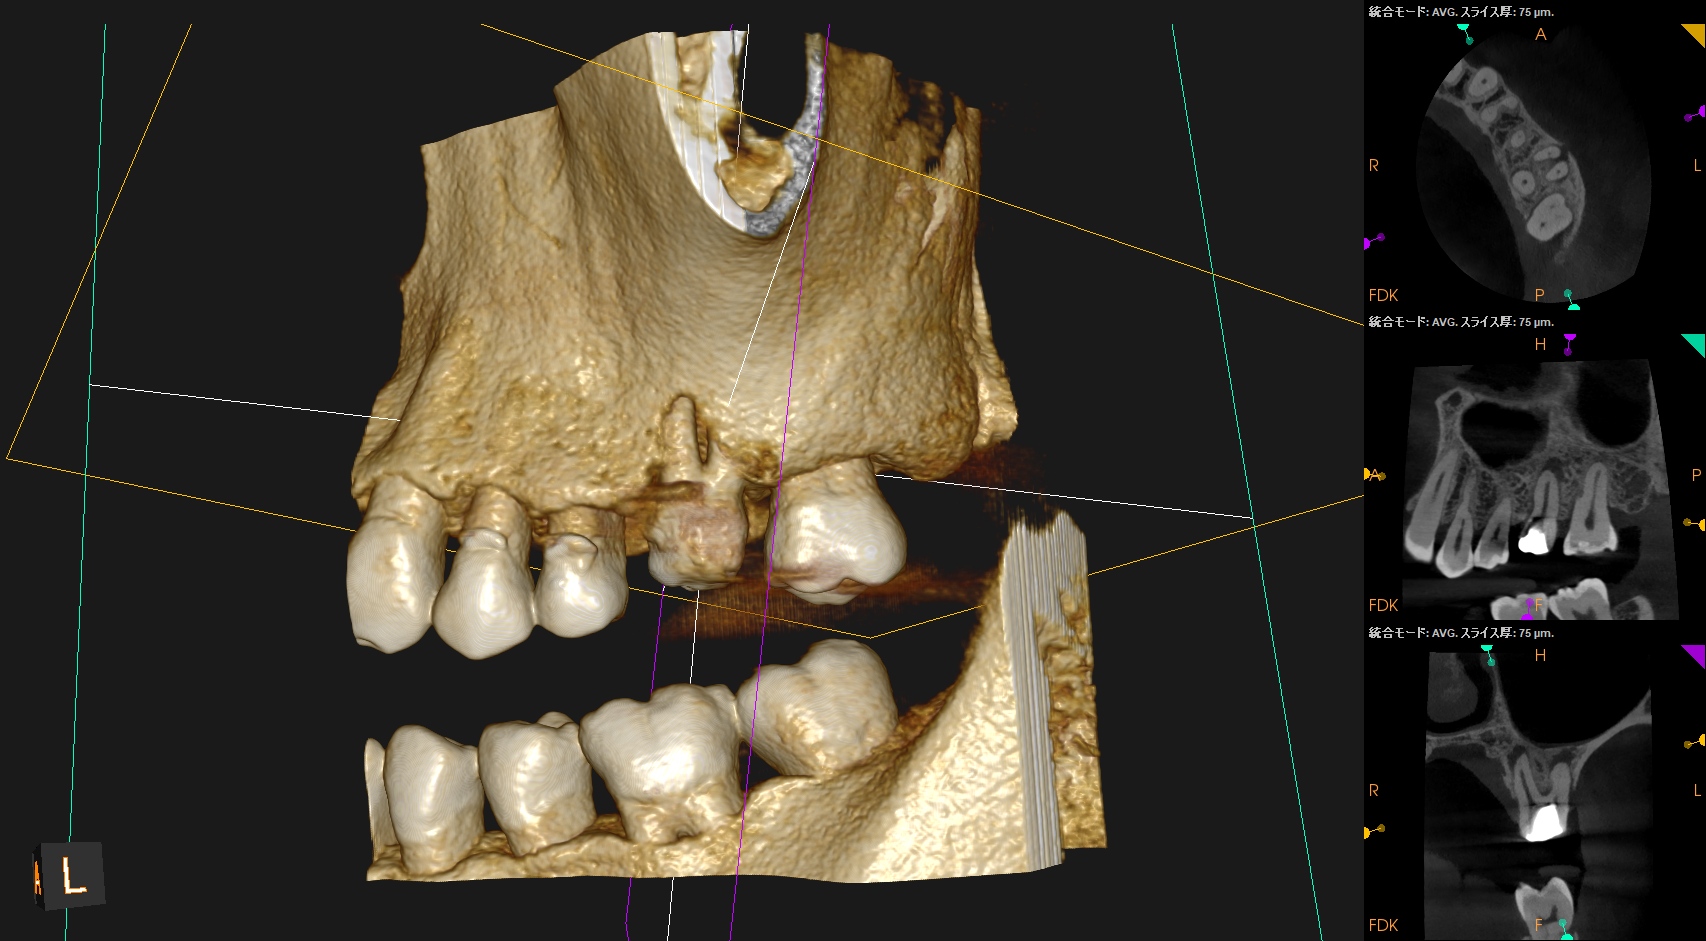

CBCT(2024.6.21)

MB

治療する前から、この#14にはMB2はないということがわかる。

理由はこの画像だ。

歯根の中央に根管があることがわかる。

1根管だろう。